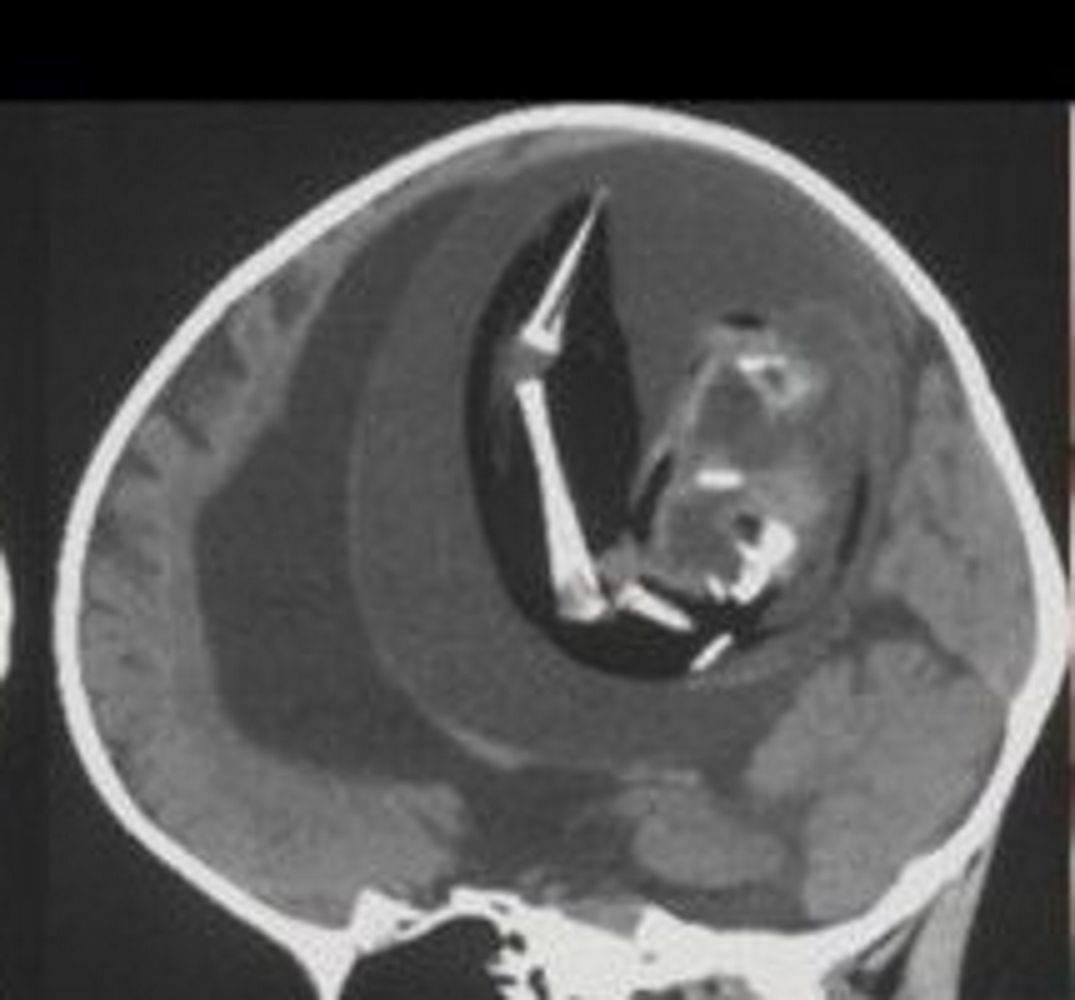

Magazyn naukowy "Neurology" opublikował opis przypadku chińskiej dziewczynki, która miała dość nietypowe objawy: powiększoną głowę oraz problemy z motoryką. Kiedy lekarze z Fudan University w Szanghaju zobaczyli wyniki tomografii komputerowej, od razu zaczęli przygotowywać się do operacji.

W czaszce dziecka znajdowała się dziwna masa, która uciskała mózg i powodowała nagromadzenie się płynu. Dopiero późniejsze badania wykazały, że był to jej… bliźniak. Płód został wchłonięty na wczesnym etapie ciąży przez silniejszego bliźniaka.

"Proszę zwrócić uwagę na ten skan. Widać wyraźnie wodogłowie, ściśnięty mózg, a także płód z kręgosłupem, kością udową i piszczelem. Masa płodowa ma kończynę górną i palce" – napisał na Twitterze Oren Gottfried, neurochirug.